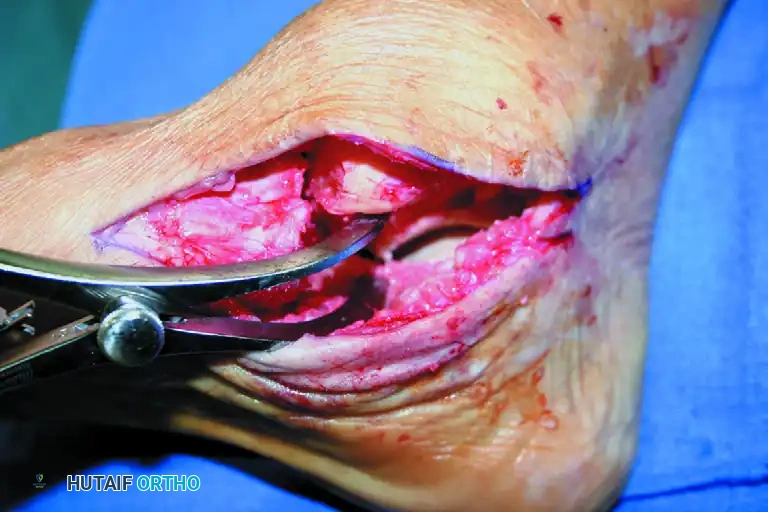

- Cartilage Removal: Use a combination of curved and straight osteotomes, curettes, and a lamina spreader to expose and débride the talonavicular joint, the subtalar joint, and the sinus tarsi. Pay special attention to the lateral aspect of the talonavicular joint, which can be difficult to visualize from the medial side.

- Subchondral Preparation: Remove all eburnated or sclerotic subchondral bone down to healthy, bleeding, cancellous bony surfaces. Small, thin osteotomes are highly effective for this delicate work.

Figure C: All eburnated or subchondral bone is meticulously removed from the talonavicular joint to expose bleeding, cancellous bony surfaces.